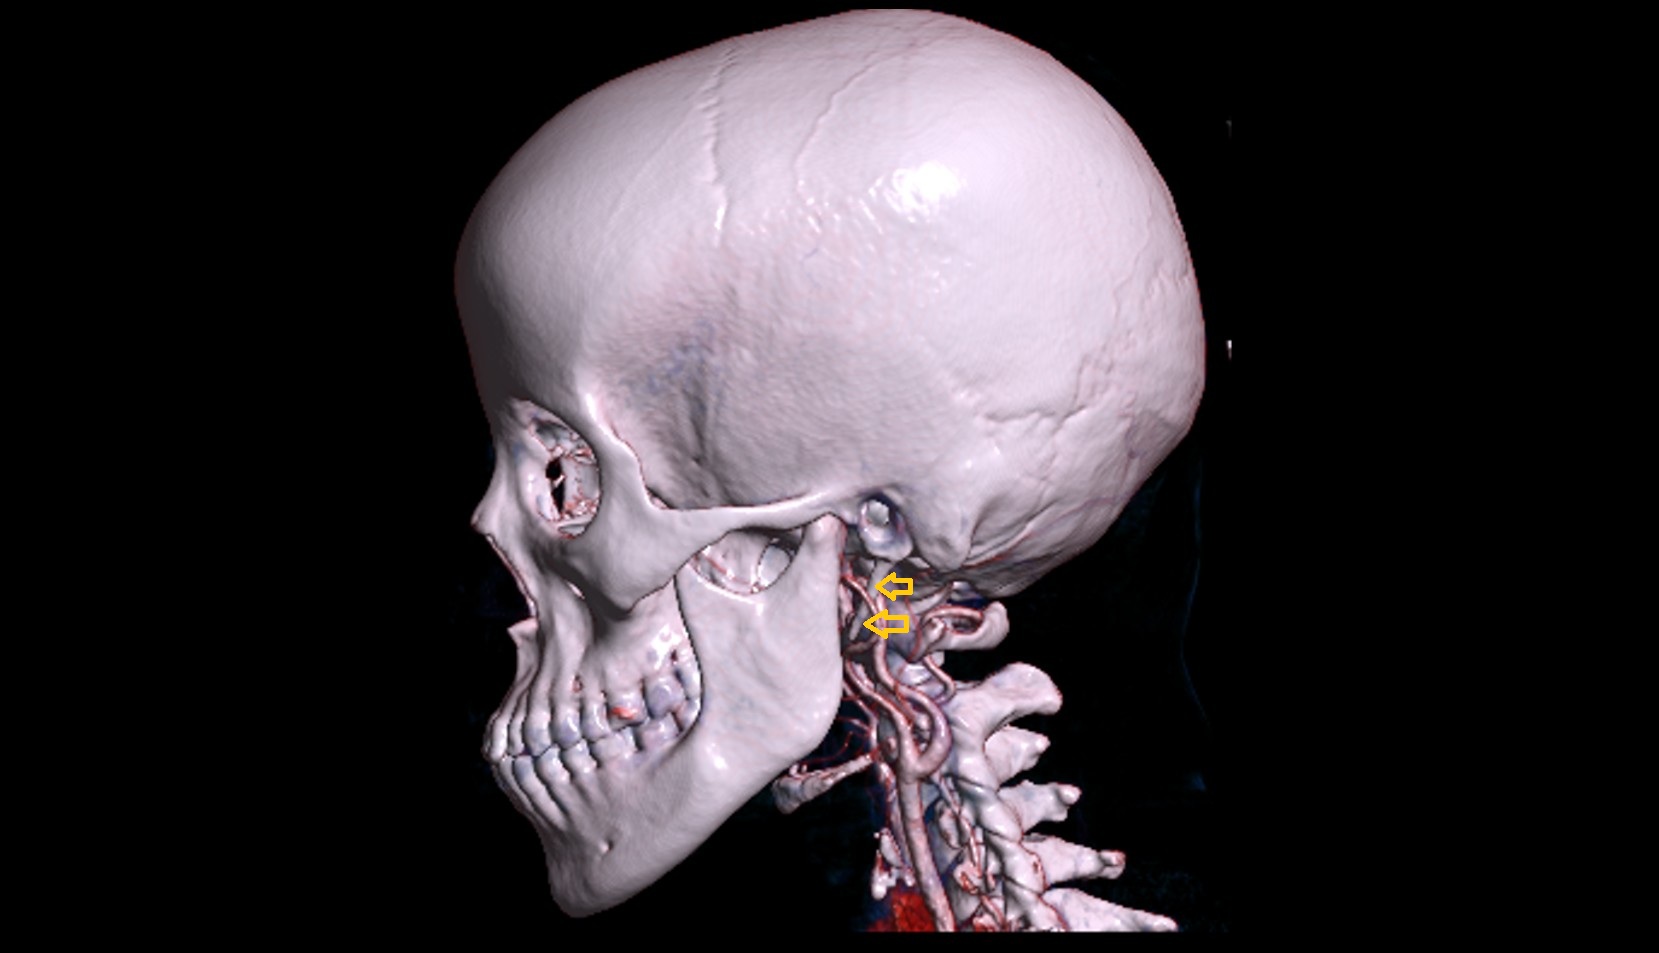

- Temporomandibular joint

- Mandibular condyle

- Mandibular fossa

- Superficial temporal artery